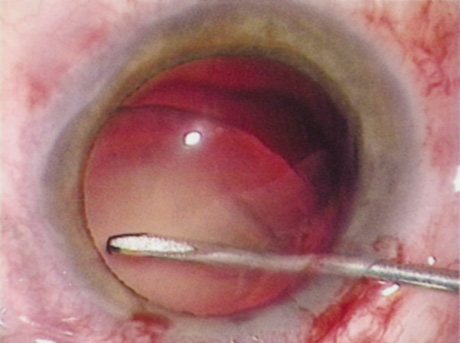

HYDRODISSECTION

Hydrodissection can be performed after the surgeon has successfully completed capsulorrhexis.97 If the capsulorrhexis is not intact, fluid forced around the interior of the capsule may cause the bag to splay open. With capsulorrhexis, hydrodissection is a safe and extremely useful maneuver. Hydrodissection can be thought of as two maneuvers: hydrodelineation and cortical cleaving hydrodissection. By placing a 27-gauge cannula on a syringe filled with balanced saline solution (BSS), the surgeon can direct fluid beneath the residual anterior capsular rim to create a cleavage plane. Depending on the direction the fluid wave takes, different lamellae of the cataract will be separated. Hydrodelineation is the term used when the cleavage plane separates the adult nucleus from the fetal nucleus or the adult nucleus from the more peripheral epinucleus. Hydrodelineation often results in the characteristic golden ring sign (Fig. 11). Cortical cleavage occurs when the cortex is separated from the capsular bag (Fig. 12). Finding the cortical cleavage plane may be facilitated by gently lifting the capsular margin away from the cortex with the BSS cannula before injecting. Several small bursts of fluid allow the surgeon to monitor progress of the fluid wave. When dealing with a soft nucleus, the authors strive to perform true cortical cleaving hydrodissection. For a hard nucleus, hydrodelineation allows manipulation of less of the nuclear bulk, although the remaining epinuclear shell must be addressed in an additional step. Hydrodelineation is particularly useful if the nucleus is not freely mobile after cortical cleaving hydrodissection.

Fig. 11. A crisp “golden ring” is seen from the fluid cleft between the epinucleus and nucleus with hydrodelineation.

Fig. 12. Hydrodissection, performed subincisionally with a 27-gauge J-cannula, produces a cleavage plane between the capsule and the cortex. The small blue arrows indicate the advancing fluid wave.